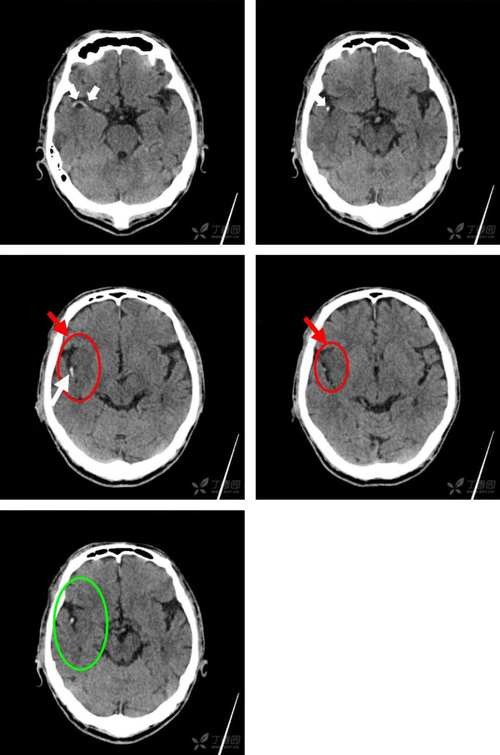

评估早期梗死征象

- 在发病早期,虽然看不到明确的低密度灶,但经验丰富的医生可以寻找一些“早期梗死征象”,

- 大脑中动脉高密度征: 提示该动脉主干有血栓形成。

- 脑沟模糊/消失: 提示局部脑水肿。

- 脑室受压: 提示大面积脑水肿。